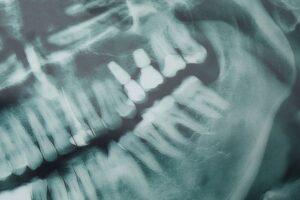

Dental implants are small titanium posts placed into the jawbone to replace missing tooth roots. A typical implant has three parts: the implant (the screw in the bone), the abutment (connects the implant to the tooth), and the crown (the visible tooth). Implants differ from bridges and dentures because they fuse with bone and act like real roots, preserving bone and feeling more stable. If you’re looking for dental implants near Paragould, AR, implants often offer the most durable, natural-feeling solution.

Your first visit includes an exam, medical history, and 3D imaging to assess bone and plan implant placement. Expect digital impressions and treatment options that fit your health and goals. Planning helps reduce surprises and shortens treatment time for dental implants paragould ar patients.